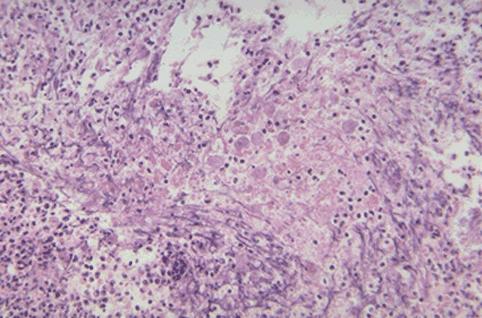

아메바 적리

소융기를 형성한 아메바적리예

염증성 및 궤양성질환/아메바성 대장염

대장/직장

마이크로